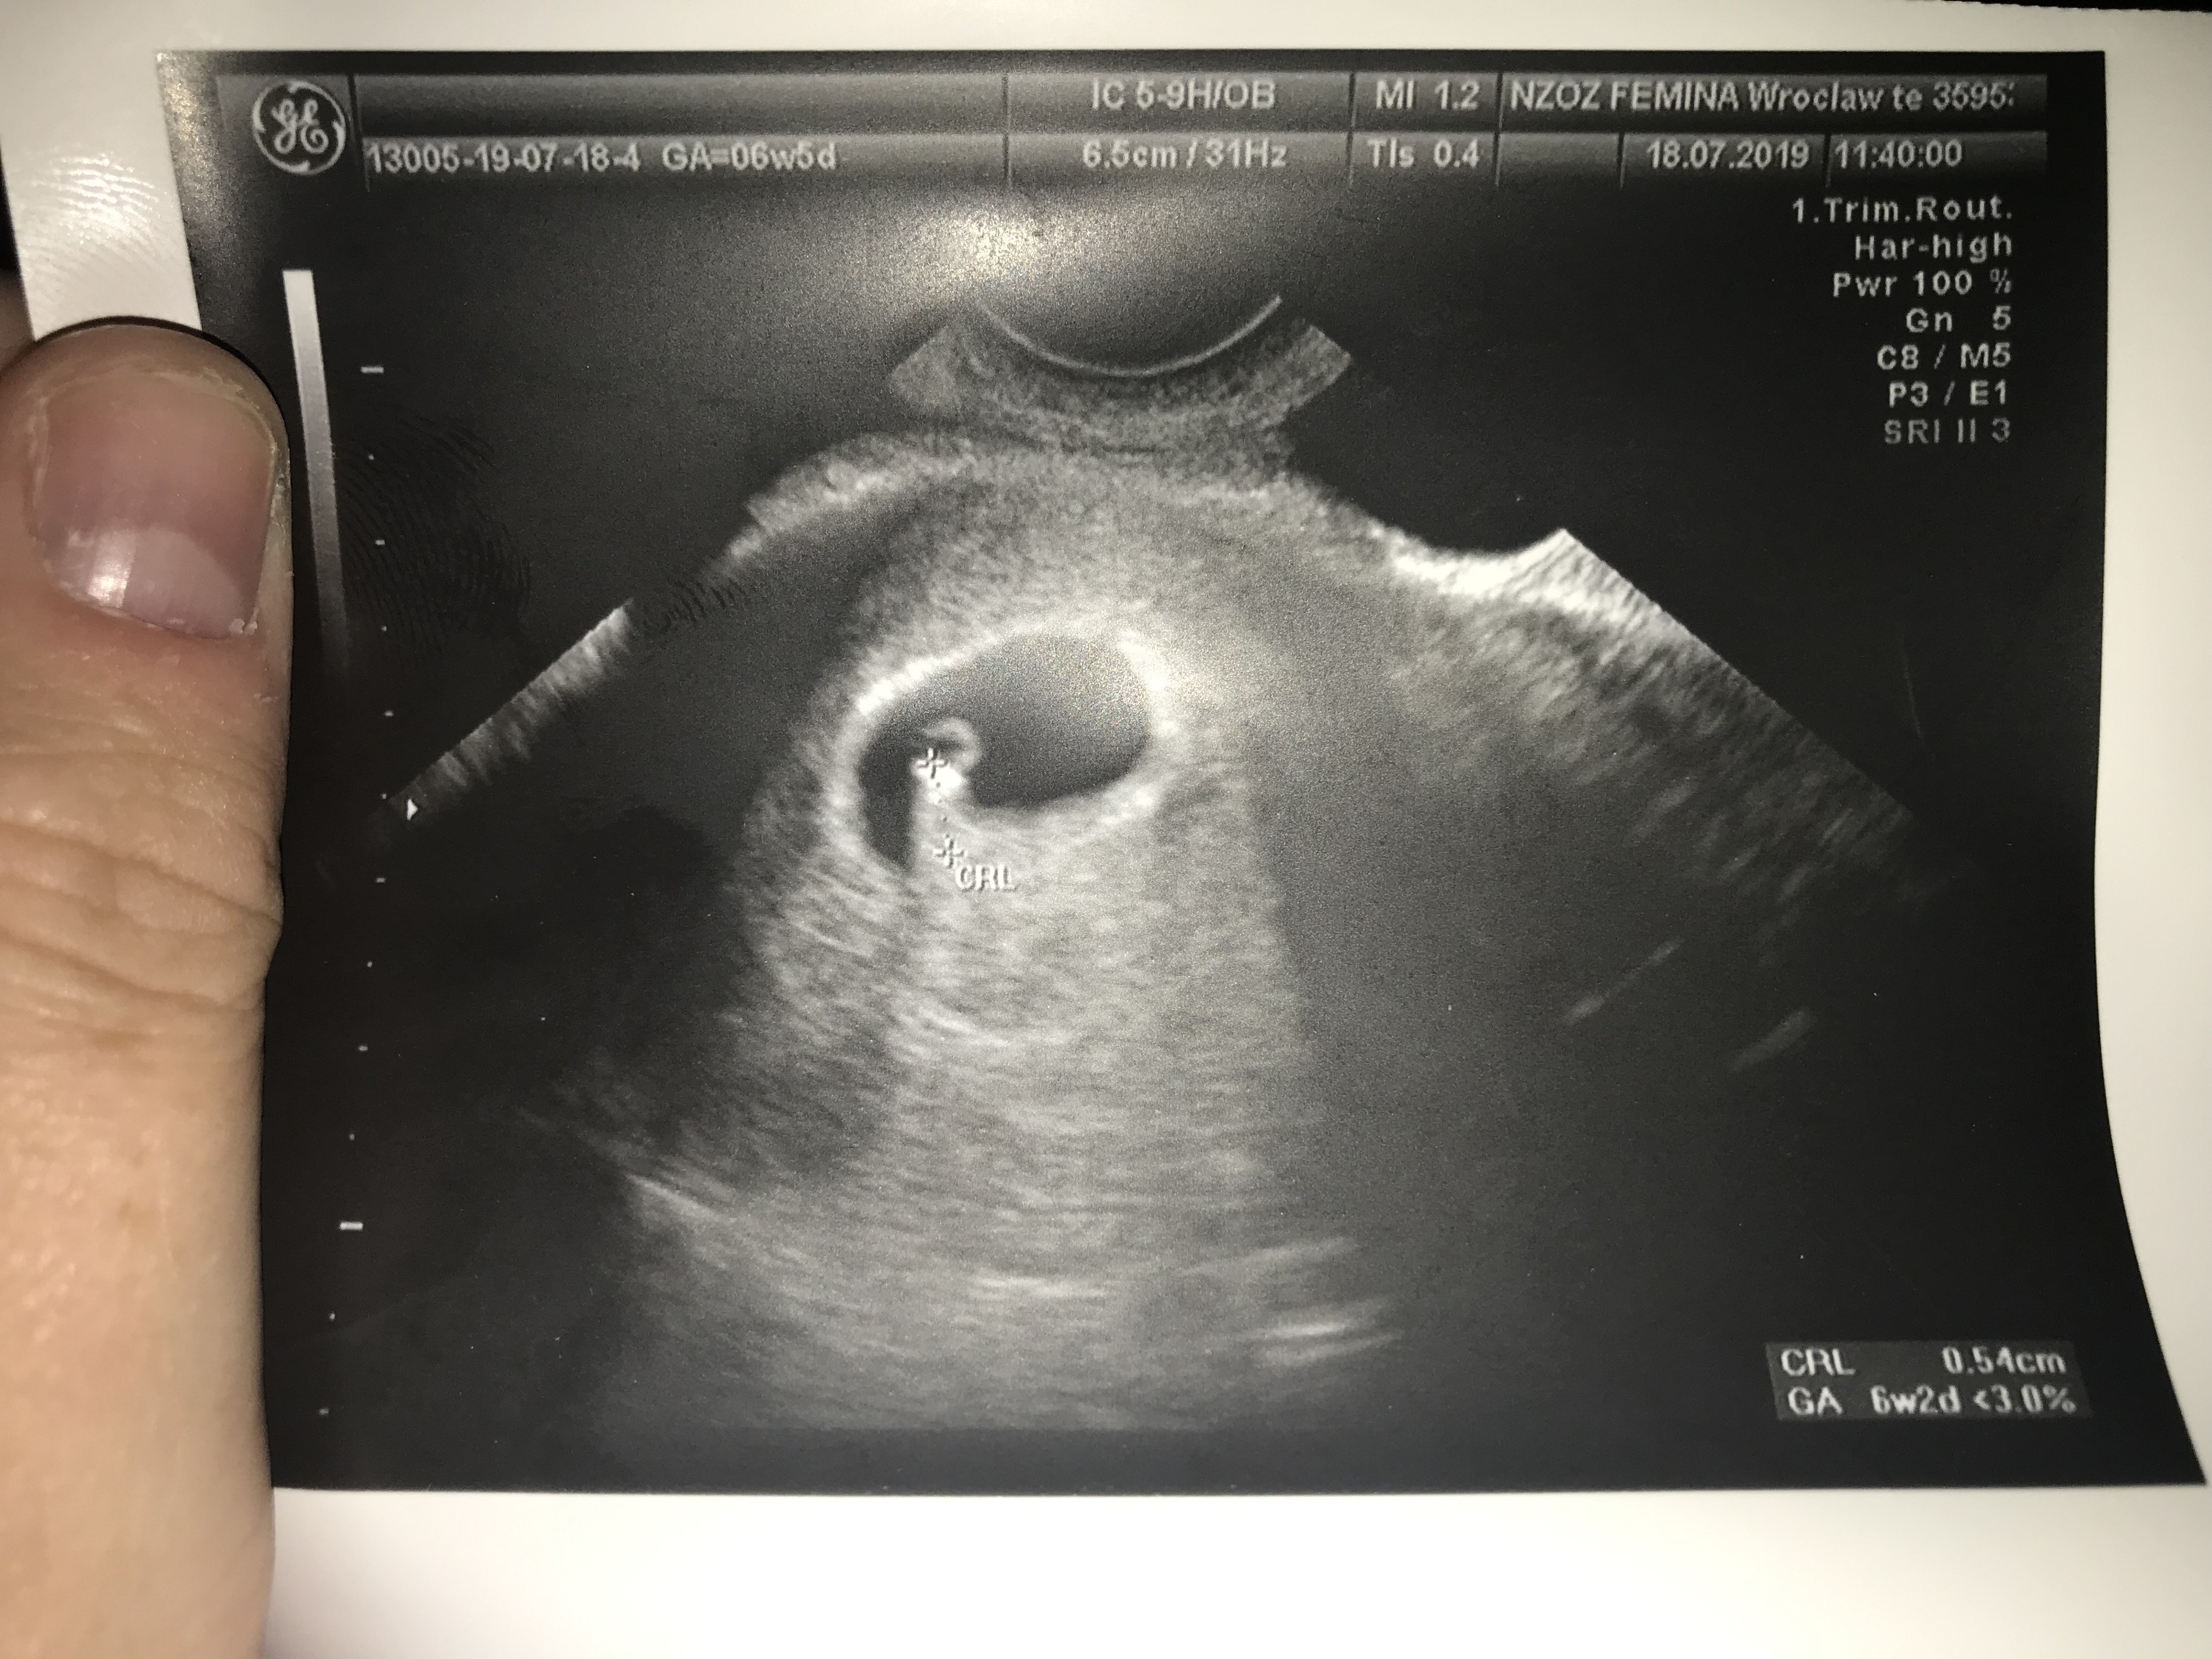

Byłam dzisiaj u ginekologa na USG, generalnie lekarz, niemrawy jak cholera... nie mowa... powiedział, ze jest płód... serca są prześwity bo to jeszcze za wcześnie... założył kartę ciąży... i dał zdjęcie. Chciałabym chociaż sama te skróty jakoś rozszyfrować żeby wiedzieć czy jest wszystko dobrze

Załączniki

• 4C925FFD-F8EE-4D83-812F-9DA392A11A52.jpeg

4C925FFD-F8EE-4D83-812F-9DA392A11A52.jpeg

1,9 MB · Wyświetleń: 86